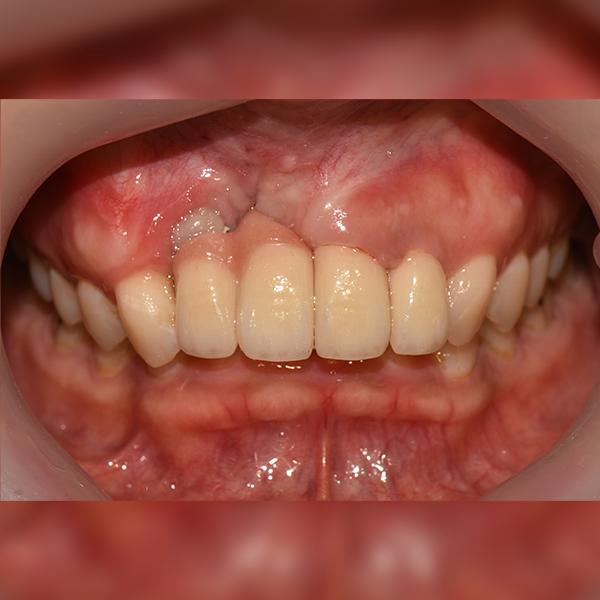

3. 案例.111 30多歲 趙*善 2018-11-30 / 2019-12-10

上顎 / 前牙部位 / 3顆以下 / 補骨

案例.111 30多歲 趙*善 2018-11-30 / 2019-12-10

After After

Before Before